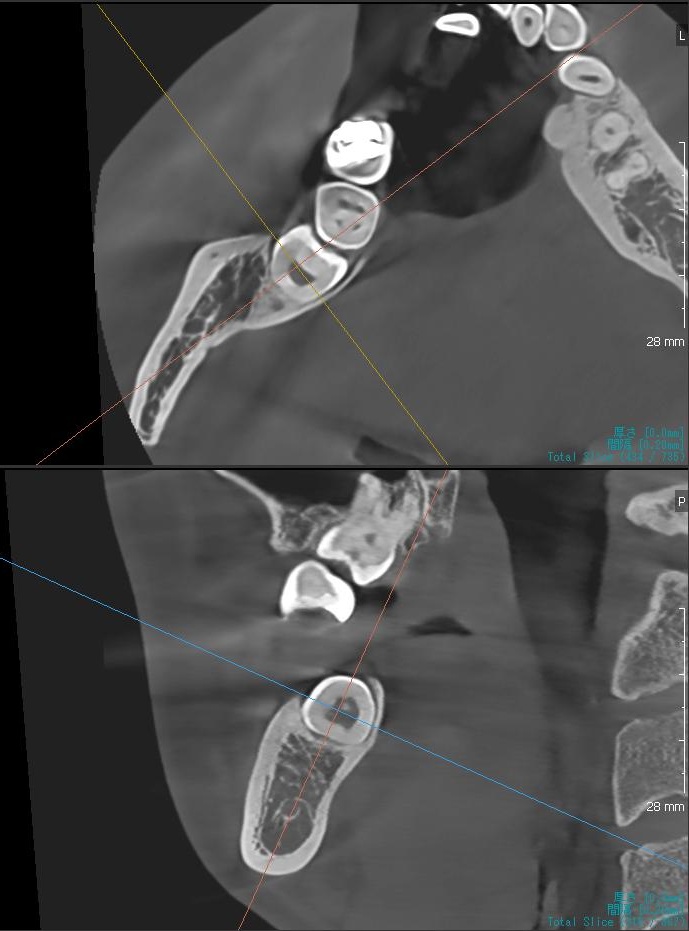

さらに、下顎の親知らずは下歯槽神経に非常に近いところに生えている場合もあるため、CTも撮影し詳しい解析を行います。

親知らずが生えている位置が、神経に近い、あるいは神経に当たっている場合は、大きな病院に紹介する場合もあります。

親知らずの根っこは下歯槽神経から近い距離にありますが、抜歯は可能との診断でした。